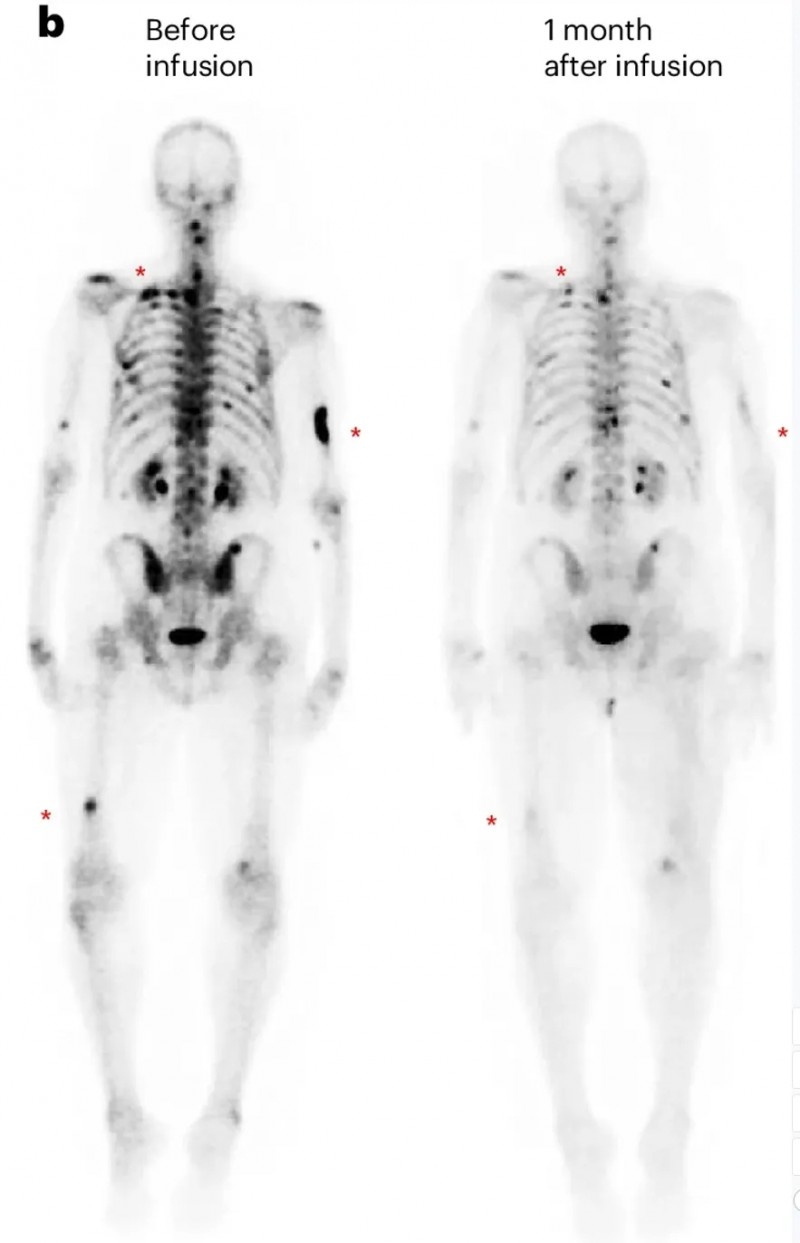

第一例为DL3剂量组患者(UPN394),其肝转移负荷实现放射学改善,但未达到PSA反应;CT扫描清晰呈现了输注前的肝转移灶,以及输注PSCA-CAR-T细胞1个月后的疾病反应(详见下图c)。

▲图源“Nature Medicine”,版权归原作者所有,如无意中侵犯了知识产权,请联系我们删除

另一例为前列腺癌伴胰腺转移患者(UPN388):输注PSCA-CAR-T前后的CT复查显示,输注前病灶大小为40.2×24.8mm,输注后1个月病变完全消退、已无法测量(详见下图e);尽管因存在骨转移,RECIST评估结果为“病情稳定”,但患者软组织转移灶的放射学表现已有所改善(详见下图b)。